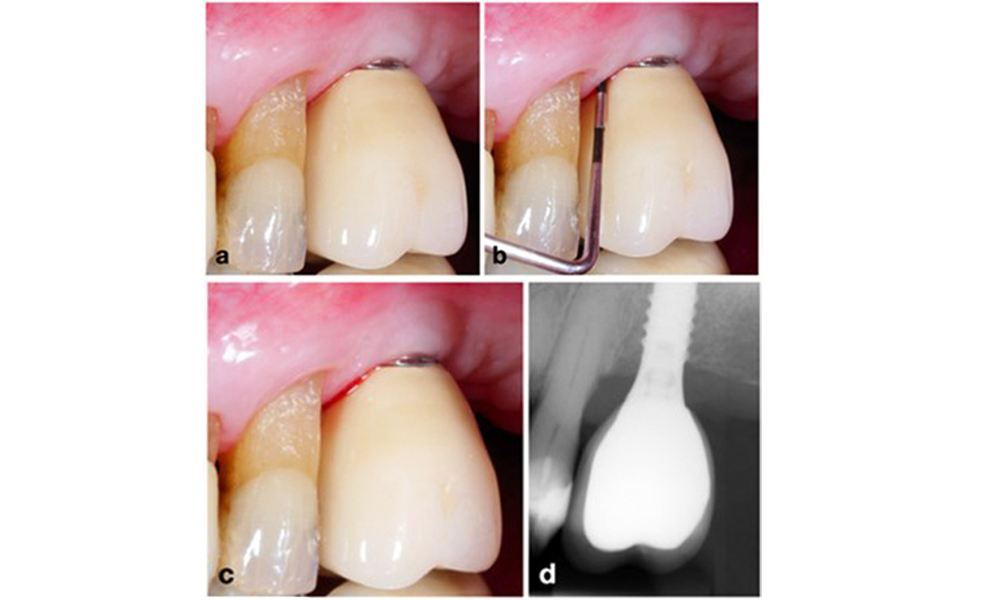

The World Workshop on the Classification of Periodontal and Peri‐Implant Diseases and Conditions from 2017 established diagnostic criteria for peri-implant mucositis and peri-implantitis (Renvert et al. 2018). Peri-implant mucositis is defined as (1) presence of inflammation around the implant (i.e., redness, swelling, line or drop of bleeding within 30 seconds of probing), combined with (2) no additional bone loss after initial healing (figure 1).

Peri-implantitis is identified by (1) signs of inflammation similar to mucositis, (2) radiographic evidence of bone loss after initial healing and (3) an increase in probing depth compared to measurements taken shortly after placing the prosthetic reconstruction (figure 2). In the absence of previous radiographs, radiographic bone level of ≥ 3 mm along with bleeding on probing and probing depths ≥ 6 mm, indicates peri‐implantitis.

The expected bone loss after initial healing attributed to marginal bone remodelling, varies based on factors such as the implant system or type. For instance, 1–2 mm bone loss is generally considered “normal” for bone level implants with an external connection (figure 2d, implant in position 23).